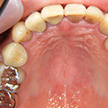

15. セラミック冠セット時上顎

初診時と比較してPCR(歯ブラシなどによるセルフケア)がしやすいシンプルな歯列と思われます。これならば2次カリエスや歯肉炎などは予防しやすいと考えます。自費診療は「歯がいくら」ではなく、いかにその患者様に自身のエネルギーを注ぐかで決定されるものと、再確認させていただく私にとっては重要な症例でした。右上3番が若干あと戻りしているのがうかがえますが、今後はリテーナー等で補正していきます。

18. 術後X線写真

初診時X線パノラマ写真と比較してレントゲン上でもシンプルだと考えます。4番の近心側のPCR等は注意して、今後の定期健診に期待いたします。